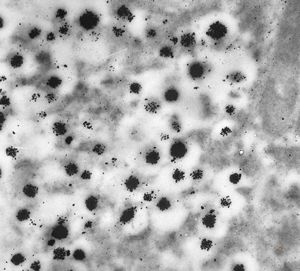

F, 44y. | carcinoid

F, 45y. | carcinoid … liver metastasis